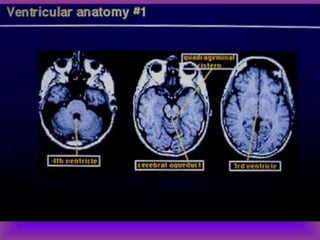

Landmarks

• Axial views

– Fourth ventricle

– Petrous bone and sphenoid ridge

– Aqueduct

– Third ventricle

– Lateral ventricles

– Frontal horns

• 104.

Landmarks • Axial views –Fourth ventricle – Petrous bone and sphenoid ridge – Aqueduct – Third ventricle – Lateral ventricles – Frontal horns – Calcifications in the choroid plexus, pineal, basal ganglia and falx – Caudate, putamen and globus pallidus